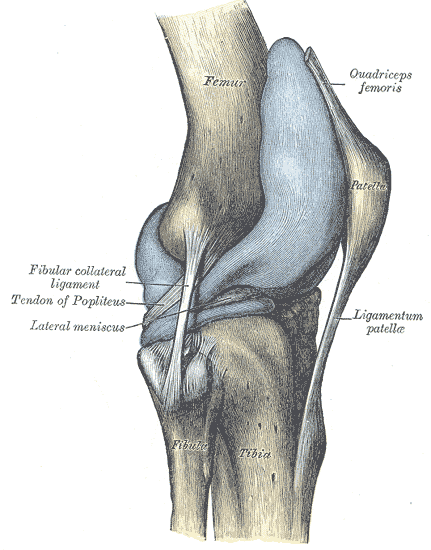

膝関節

これは通常、2つ以上の靭帯損傷(ACL、PCL、側副靭帯)を伴う。

- 腓骨筋、脛骨筋(神経支配筋の機能低下)、後脛骨筋および/または足背筋の損傷(拍動のため触診を行う)

- 大腿四頭筋に触知可能な溝がある。

- 両膝蓋骨の高さの違い(アルタ:膝蓋腱が冒された、バチャ:大腿四頭筋腱が冒された)